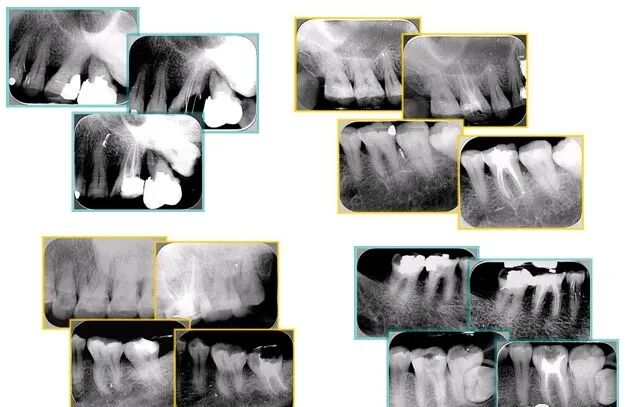

左图和上图为干髓治疗后牙齿,龋齿疏通后进行根管充填。

如图为塑化加根充处理后牙齿 X 线片▼

牙胶尖什么颜色最全整理 | 根管治疗标准步骤和细节把握_https://www.jmylbn.com_新闻资讯_第33张